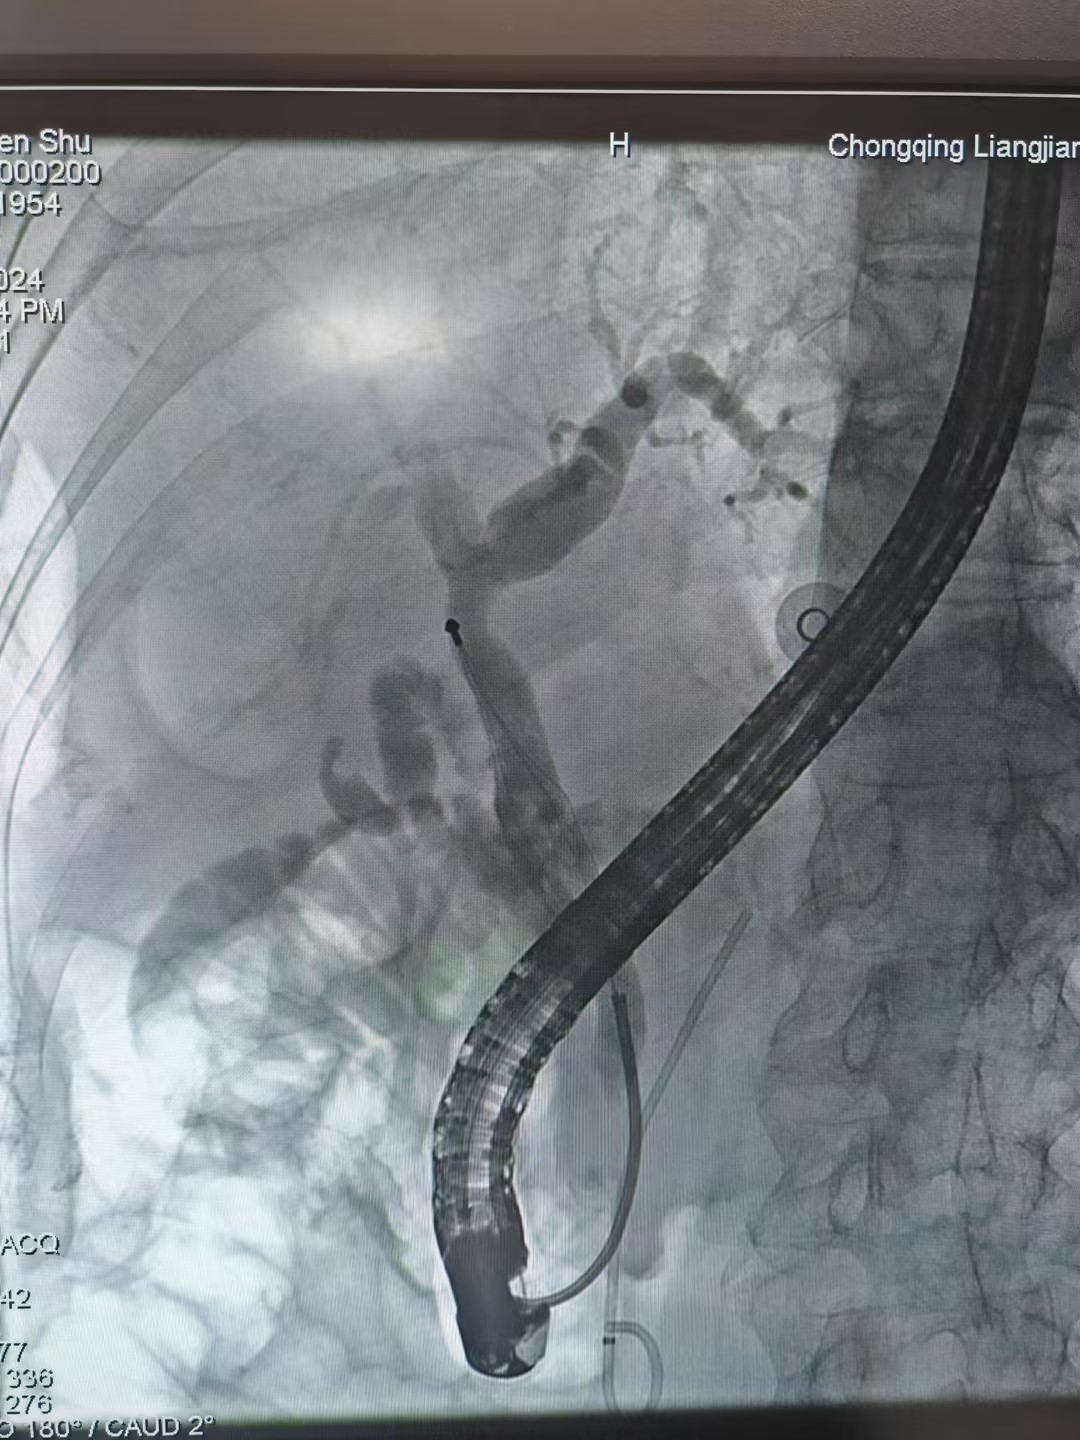

近日,重庆两江中医院脾胃病科成功为70岁患者唐大爷实施了ERCP(经内镜逆行胰胆管造影术)胰管支架植入术和取石术两次手术,患者术后恢复良好,于近日治愈出院。

唐大爷起病当日腹痛难忍,来我院门诊就诊。检查发现胆总管结石。医生表示,这类疾病一般以手术为主,但考虑到唐大爷的年纪,加上其伴有血友病等多重基础疾病,无法忍受手术。于是脾胃病科医疗团队紧急开会制定治疗方案,最后决定先为其采用ERCP(经内镜逆行胰胆管造影术)胰管支架植入术进行治疗。

术前,脾胃病科和手术麻醉科医护团队详细地评估患者病情,并制定周密的手术计划。术中,脾胃病科副主任、副主任医师徐杨凭借多年的经验,准确定位到患者病变处,在成功地置入1根胰管支架后,顷刻便看到白绿色脓性分泌物喷涌出来。随着脓性分泌物的排出和胆道梗阻的解除,患者原本的高热症状得到明显缓解。这表明治疗取得初步成效,病情正在向好的方向发展。